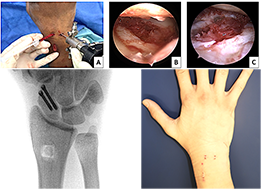

• Focus of the Hand surgery research: development of mini-invasive treatment modalities using arthroscopy in carpal injuries and evaluation of innovative modalities in repair of peripheral nerve injuries.